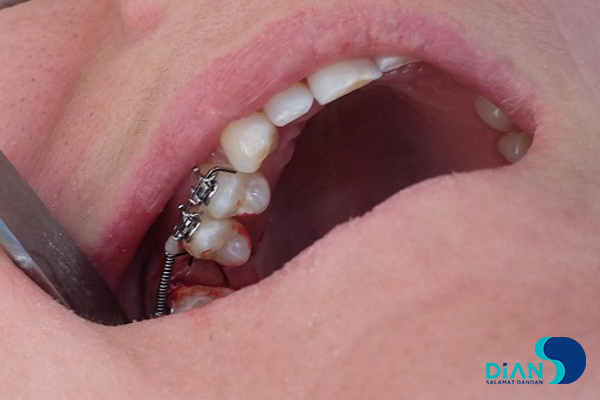

Implantation in Molar Area

The experienced dentist Dr. Müesser Aktaş from Turkey successfully performed a dental implant procedure using Bio3 Implants in the molar region. For this operation, Dr. Aktaş utilized the Bio3 surgical kit, which is specifically designed to provide precision, ease of use, and efficiency during implant placement. The system’s user-friendly design and reliable components allowed for a smooth and accurate procedure, ensuring optimal results for both the patient and the clinician. This case once again highlights the practicality and advanced engineering of Bio3 Implants, making them a trusted choice for dental professionals worldwide.